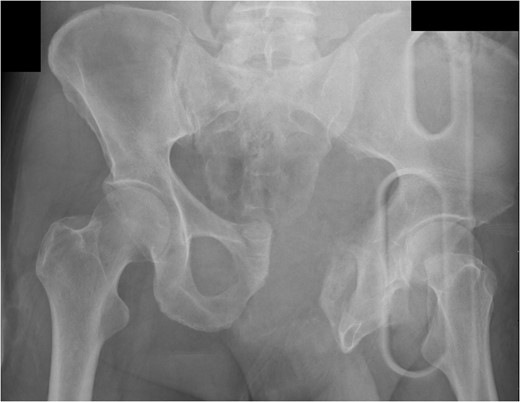

A 55-year-old male arrived at the ER, a large tree having fallen across his pelvis. The patient was hypotensive at the scene. He received over 1500 ml of crystalloid in route to the emergency room. Upon arrival to St. Mary’s Medical Center, the patient had a systolic pressure of 70. His heart rate was in the 130 s. The patient was awake and alert. A left subclavian central line was placed and he was transfused with two units of O-blood. The patient’s abdomen was soft and nontender. The patient had blood at his meatus. The patient’s pelvis was tender to palpation. His left leg was cold, mottled and pulseless. There was no femoral pulse on the left side. The chest x-ray was normal, however, the pelvis film revealed extreme widening and displacement of the symphysis pubis (Fig. 1). A bedsheet was wrapped around the patient’s pelvis and another two units of O-packed red blood cells were administered. Additionally, he was given four units of fresh frozen plasma. The patient was started on norepinephrine to control his persistent hypotension. His systolic blood pressure rose into the mid-90s and the patient was taken to the CT scanner. The CT scan revealed that the patient had an acute occlusion of his left iliac artery, as well as a large left iliac wing fracture with a massive associated hematoma. A right iliac wing fracture was located near the sacroiliac joint. There was pubic diastasis, as well as a left superior rami fracture with a modest associated hematoma. There was no extravasation of dye (Figs 2 and 3). The patient was taken directly to the operating room because he was developing significant abdominal distention in the face of continued hypotension. Anesthesiologists placed a second large-bore central line for fluid resuscitation. An exploratory laparotomy was performed, revealing an intraperitoneal bladder rupture. The patient was bleeding freely from his pelvic hematoma. Multiple attempts were made to pack the pelvis tightly with laparotomy pads, but efforts were unsuccessful. Because of the distorted anatomy obtaining proximal and distal control of the iliacs was extremely difficult. The patient suffered massive retroperitoneal venous bleeding, which we were unable to control. The patient exsanguinated on the operating room table; despite having received over 30 units of packed red blood cells, 30 units of fresh frozen plasma, several 10 packs of platelets, cryoprecipitate and factor VII A.

Large retroperitoneal hematoma. Arrow depicts injured left iliac artery.